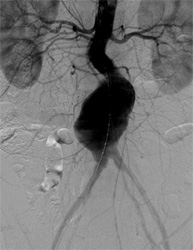

血管造影検査

従来、放射線診断に用いられていた血管造影はCTやMRIの発展にともない、現在では主として治療目的のために行われています。この手法はIVR(インターベンショナル・ラジオロジー)と呼ばれています。

当院の血管造影室には、全身用にAlluraXperFD20、心臓血管造影用にはAlluraXperFD10/10(いずれもフィリップス社製)が導入され、フルデジタル化により再現性の高いデータを迅速に参照できるようになり、より精度の高い検査と治療を行っています。

大動脈ステントグラフト

治療前   治療後